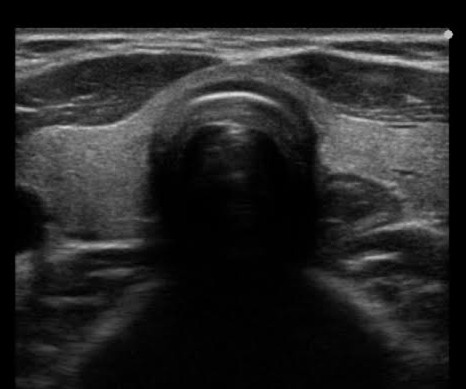

正常な甲状腺超音波検査画像

甲状腺の大きさや形、結節の有無などを確認します。バセドウ病や橋本病では特徴的な画像所見を示すことが多く、また、甲状腺腫瘍などはエコー検査でないと発見できないことも多いです。